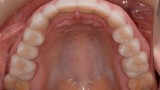

W pierwszym etapie diagnostycznym wykonano zdjęcia zewnątrz- i wewnątrzustne (ryc. 1-12).

Wykonano także modele diagnostyczne zaartykulowane w relacji centralnej (RC), którą zarejestrowano ze względu na zwiększone napięcie mięśniowe z wykorzystaniem deprogramatora Koisa (ryc. 13-15), oraz zdjęcie pantomograficzne (ryc. 16) i cefalometryczne. Analiza modeli w RC wykazała przesunięcie żuchwy w kierunku doprzednim w stosunku do pozycji maksymalnego zaguzkowania i przedwczesne kontakty funkcjonalne na zębach bocznych, co tłumaczyło obecność odprysków szkliwa na brzegach siecznych górnych zębów (szczególnie wyraźne na zębie 12) (ryc. 14, 17). Na modelach wykonano studium funkcjonalne mające na celu określenie, w jaki sposób można odtworzyć prawidłową funkcję, tzn. uzyskać prawidłowy nagryz pionowy i poziomy oraz prowadzenie przednie (ryc. 18-20).